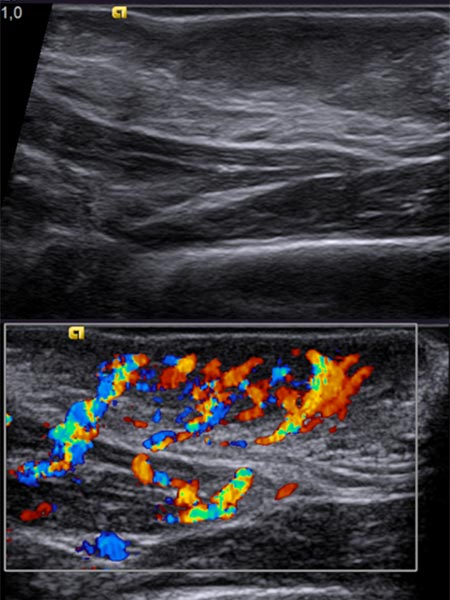

On B-scan ultrasonography (top image), the tumor is relatively homogeneous, hypoechoic, and clearly solid, not compressible. Color-coded duplex ultrasonography (bottom image) shows intense perfusion via multiple arterial vessels. This is suggestive of a congenital vascular tumor and, in this case when combined with the bluish appearance, the special case of a congenital hemangioma.

Control sonography (color-coded) at 4 months of age shows no change in echogenicity, especially no signs of involution. Continued strong perfusion and no increase in echogenicity, as would be the case with a rapidly involuting congenital hemangioma (RICH).